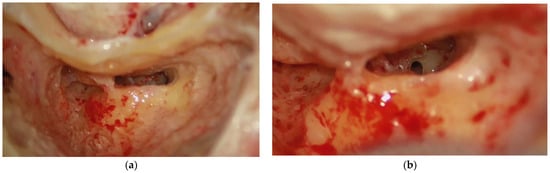

A cochlear implant is the standard treatment for patients with sensorineural hearing loss ranging from severe to profound [1]. The surgical procedure for cochlear implantation aims to atraumatically insert the cochlear implant electrode array into the cochlea. Surgeons must access from the surface of the temporal bone (Figure 1a) to reach the round window (Figure 1b). In standard procedures, this access is created by removing portions of the mastoid bone through a mastoidectomy with antro-atticotomy and posterior tympanotomy [2,3].

Figure 1. (a) Mastoidectomy with posterior tympanotomy; (b) The view of the round window through the posterior tympanotomy.